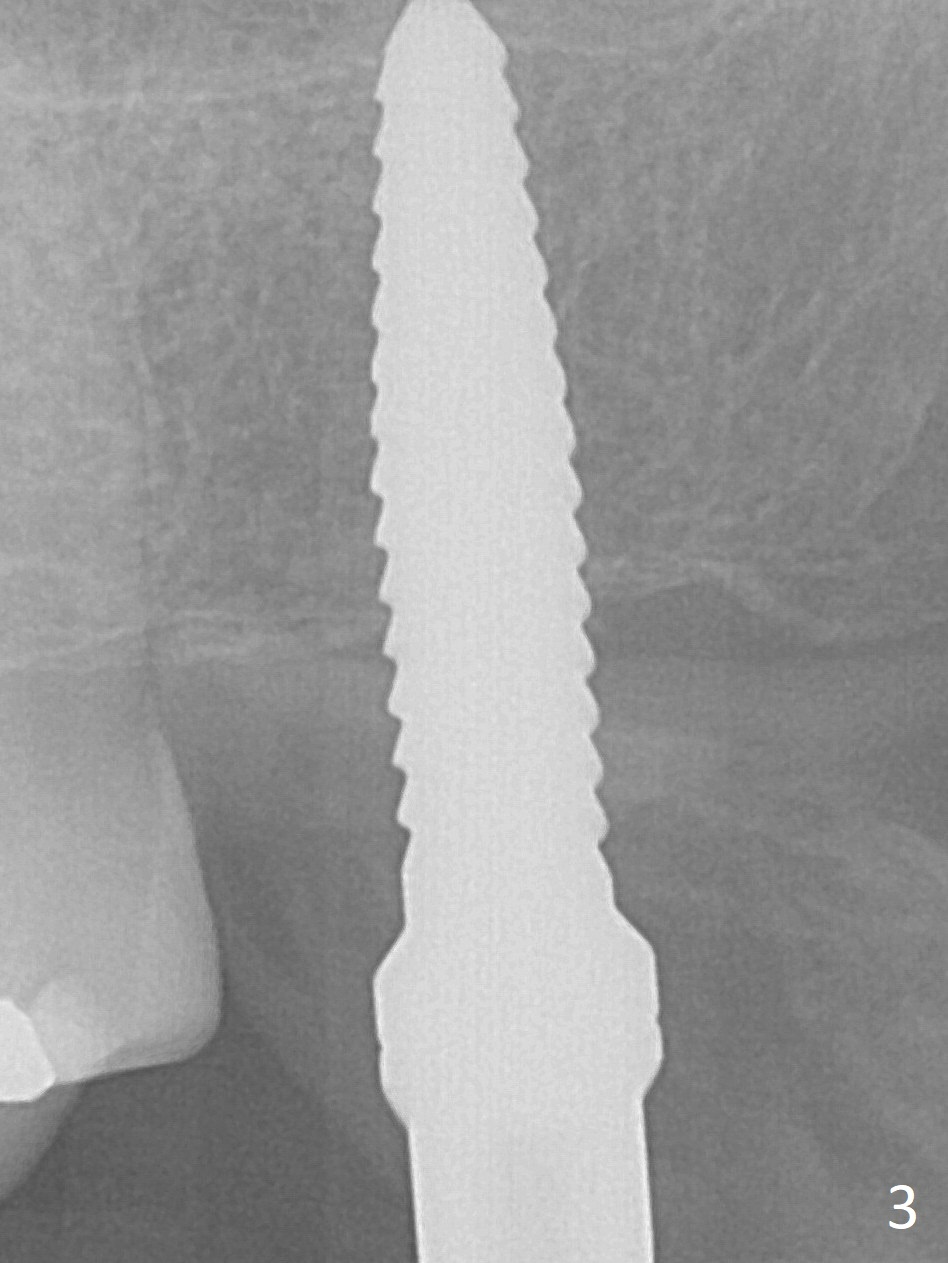

The ridge is pointed at the site of #15 (Fig.1). A 1.2 mm initial drill is used to start osteotomy for 10 mm, followed by an incision over the ridge mesiodistally for ~ 8 mm. After tapping the #15 C blade, the 1st Bone Expander 1.0/1.6 mm) is inserted for ~ 11 mm (Fig.2, 20 Ncm). Bone expansion continues until #4 Expander (2.4/3.7 mm, Fig.3). When 4x11 mm and 4.5x11 mm dummy implants are placed (Fig.4), insertion torque remains 20 Ncm. Following placing allograft with 3-4 amalgam carriers, a 5x11 mm IBS implant is placed with 20 Ncm (Fig.5,6). In fact the implant turns when an abutment is placed. When the implant is re-inserted, torque decreases to 10 Ncm. Instead a healing screw is placed. The low torque value is due to soft bone and failure to underprep. #4 Expander (Fig.3) seems larger than 4.5 mm implant (Fig.4). #3 Expander (1.7/3.1 mm) should have been used prior to definitive implant placement. The implant appears to have osteointegrated 3 months postop (Fig.7); impression is taken. The bone density at the crest increases 1.5 years post cementation (Fig.8 *, as compared to Fig.6), although there is mild bone loss. Implant placement should be deep when bone expansion is carried out. The tooth #14 develops a buccal fistula, corresponding to periapical radiolucency of the mesiobuccal root (Fig.9 white >). The abutment of #15 may be incompletely seated (black <). PA taken when RCT of #14 is finished does not show the incomplete seating of the abutment (Fig.10). Since there appears no history of abutment screw loosening, the abutment is not reseated when #14 is prepared for crown. Recall 3 years 7 months post cementation shows incomplete seating of the abutment (Fig.11 >). After crown proximal reduction (Fig.12 *) and clockwise turn of the crown, the abutment appears to be completely seated. When the case returns from lab, the separate crown and abutment cannot be connected to the fixture because of soft tissue adaptation and change in a month. The abutment is reseated to the fixture analog in the model and the crown is recemented with temp bond (in case of misalignment) while making sure that the crown has the best proximal contact with the neighboring crown. With the abutment and crown in a unit, it is much easier to reseat the abutment with normal proximal contact. The torque is 20 Ncm. The access hole is closed with Cavit.